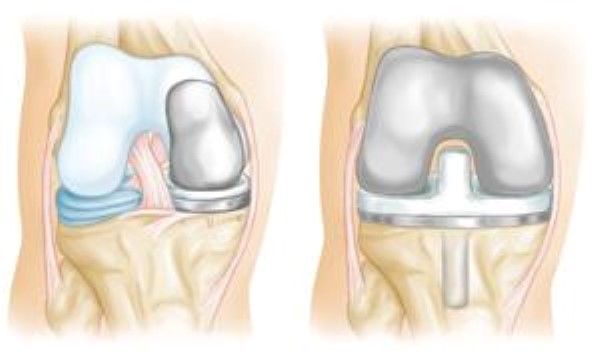

- Thay khớp gối một phần (UKR). Có thể áp dụng ở bệnh nhân trung niên, ảnh hưởng chủ yếu đến khoang trong và ít ảnh hưởng đến khoang ngoài, khớp gối vững và không đau nhiều ở trước gối, biến dạng vẹo trong có thể điều chỉnh được. Ưu điểm bảo tồn các dây chằng chéo.

- Thay khớp gối toàn phần (TKR). Chỉ định trong trường hợp thoái hoá khớp gối nặng cả ba khoang, Kết quả thường tốt cho hầu hết bệnh nhân.

- Phẫu thuật làm dính khớp gối ngày nay thường được dành cho những bệnh nhân phẫu thuật thay khớp gối thất bại và ở độ tuổi tương đối trẻ hơn với mức độ chức năng cao hơn và khả năng duỗi gối kém.

XEM THÊM: CHƯƠNG TRÌNH PHCN SAU PHẪU THUẬT THAY KHỚP GỐI TOÀN PHẦN